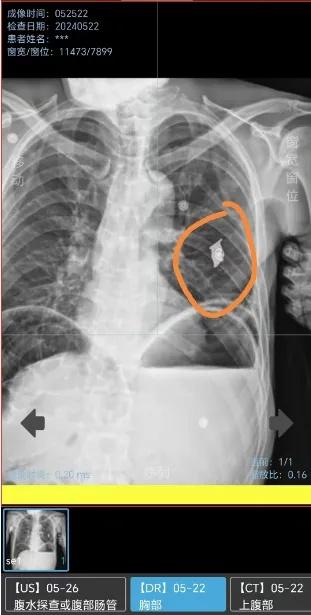

恢复了精神的赵爷爷在查房时主动和医护人员聊起了自己的过往。原来赵爷爷是一名曾三次入伍,参加过对越自卫反击战的一等功臣。在1979年的对越自卫反击战中,不幸中弹身受重伤,手术后右肺残留一个弹片。此时,医护人员心中的"疑团"才被解开,才明白老人残留在肺部的弹片所代表的意义。

"手术当天CT检查时,显示赵爷爷的左侧肺部被切除了三分之二,右肺还留有一个弹片,就隐约猜到几分。"戴主任表示,由于不是此次发病的主要原因,所以只是简单问了下情况。得知赵爷爷的故事后,大家对老人越发敬重。"那天还是我抱他上的手术台,我还感叹这个老人怎么只有80多斤,今天才明白原因。"戴少华感慨道。